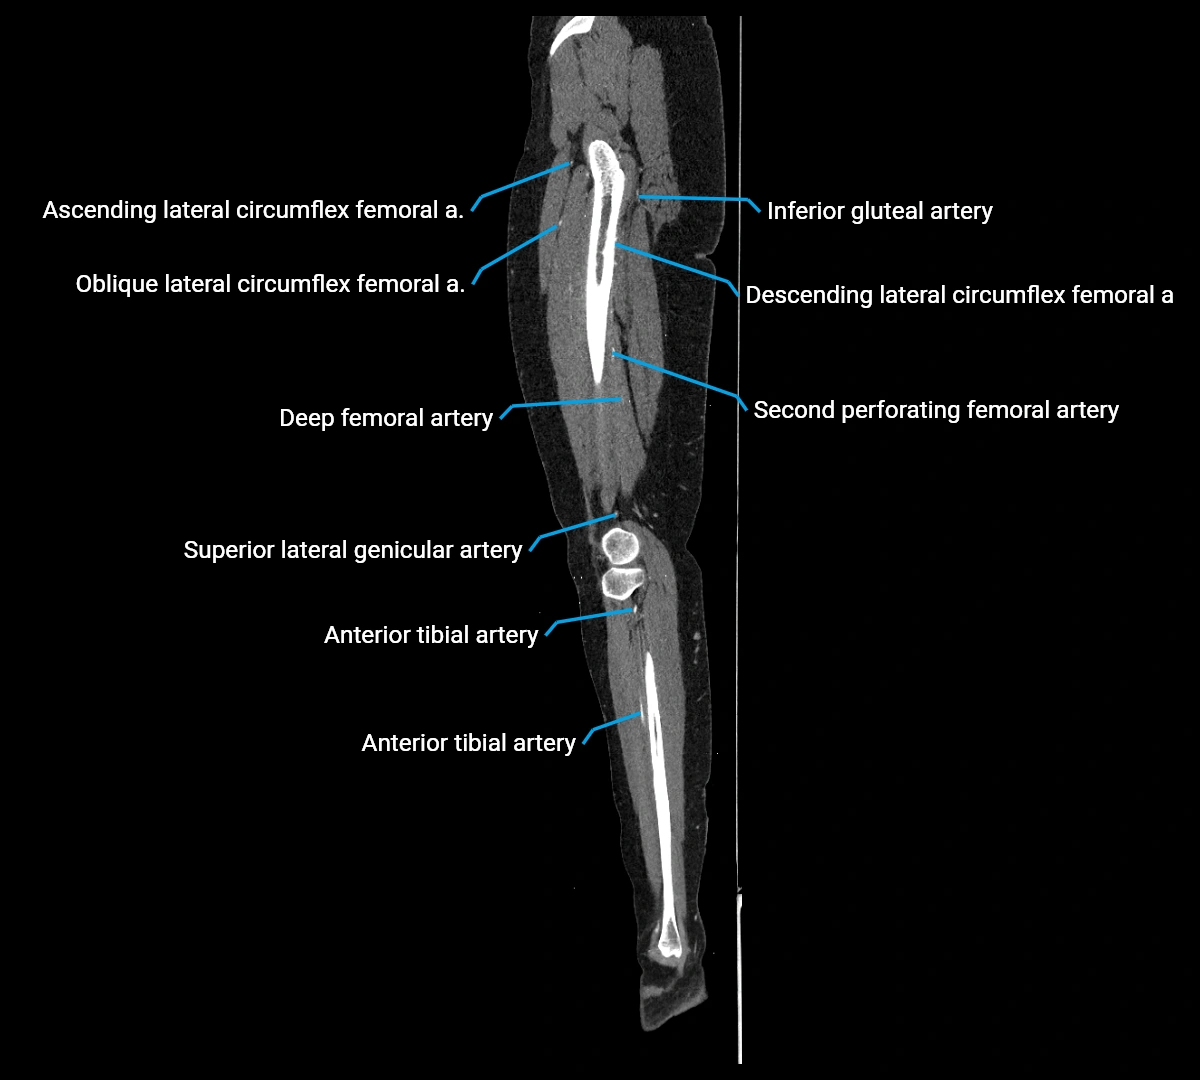

Contrast-enhanced CT (CTA):

• Gold standard for abdominal aortic imaging

• Provides excellent detail of lumen, wall, aneurysm, thrombus, and branch vessels

• Multiplanar and 3D reconstructions help in aneurysm measurement, stent graft planning, and dissection evaluation

• Detects acute rupture, traumatic injury, or occlusion with high sensitivity